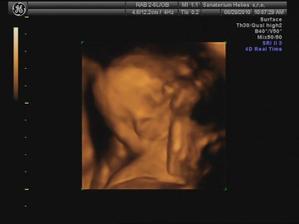

29.6. jdeme na 3D ultrazvuk 🙂 těšíme se... - bylo to úžasný 🙂 cena sice vyšší, ale jedna barevná fotka tištěná, 3 fotky na mail a téměř půlhodinové video, ze kterého jsme si doma udělali ještě asi 120 fotek 🙂

18.8. UTZ ve 30 tt - vše v pořádku, Honzíček je plně vyvynutý, má vše co má mít, srdíčko pumpuje krev jak má - nádherný zvuk 😵

váží 1620 g a odpovídá 30+2, takže TP zůstává stejný 🙂

je otočený hlavičkou dolů a s největší pravděpodobností (prý 99,9 %) tak už zůstane až do porodu 😉